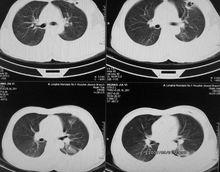

中縱隔影像圖1.心包包裹心及出入心的大血管根部。分為外層的纖維心包和內層的漿膜心包。纖維心包為一底大口小的錐形囊,囊口在心的右之方與出。入心的血管外膜相移行,囊底對向膈中心腱並與之愈著。纖維心包堅韌而缺乏伸展性,當 心包腔積液時,腔內壓力升高,可壓迫心臟。漿膜心包分為髒、壁二層,壁層與纖維。心包緊密愈著,在出入心大血管根部稍上方反折為髒層,即心外膜。慢性炎症 時,髒、壁層可粘連愈著,限制。心臟舒縮。心包腔為漿膜心包髒、壁層圍成的狹窄而密閉的腔隙。腔內有少量漿液。

心臟解剖【圖】位於升主動脈、肺動脈與上腔靜脈、左心房之間的部分,稱心包橫竇, 其大小可容一指,是心血管手術阻斷血流的部位。位於兩側肺上、下靜脈,下腔靜脈、左心房後壁與心包後壁之間的部分,稱心包斜竇,心包腔積液常積聚於此而不易引流。漿膜心包壁層前部與下部移 行處所夾的腔,深1~2cm,是心包腔之一部,稱心包前下竇,位置較低,心包積液常先積聚於此。心包前壁隔著胸膜和肺與胸骨和第2~6肋軟骨為鄰,但在第4~6肋軟骨高度因胸 膜前界形成心包三角,使心包直接與左第4~6肋軟骨前部、第4~5肋間隙及胸骨下左半部相鄰,為心包裸區,可經此部位進行。已包穿刺。心包前壁有結締組織連於胸骨,稱胸骨心 包韌帶,起固定心包作用。心包後面有主支氣管、食管、胸導管、胸主動脈、奇靜脈和半奇靜脈等,兩側鄰接縱隔胸膜,並有膈神經和心包膈血管自上而下行於心包與縱隔胸膜之間。心包下面鄰下腔靜脈和膈,與膈中心腱緊密癒合,周圍部尚 易分離。上方有升主動脈、肺動脈乾和上腔靜脈。心包由心包膈動脈、肌膈動脈和食管動脈等供血,靜脈與動脈伴行,分別匯入胸廓內靜脈、奇靜脈或半奇靜脈等。心包的淋巴注入縱隔前、後淋巴結和膈上淋巴結。心包的神經來源較多。來自信叢、肺叢和食管叢,也來自膈神經、肋間神經和左喉返神經,傳遞感覺衝動,心包手術需進行麻醉。

(l)位置和毗鄰:心位於縱隔內,被心包所包裹,前方對胸骨體下部和第2~6肋軟骨,後方平第5~8胸椎,約2/3在前正中線左側,1/3在右側。其毗鄰關係大致與心包相似,但其上界低於心包上界,出入心的大血管和肺根結構位於心的上方,並與之相毗鄰。